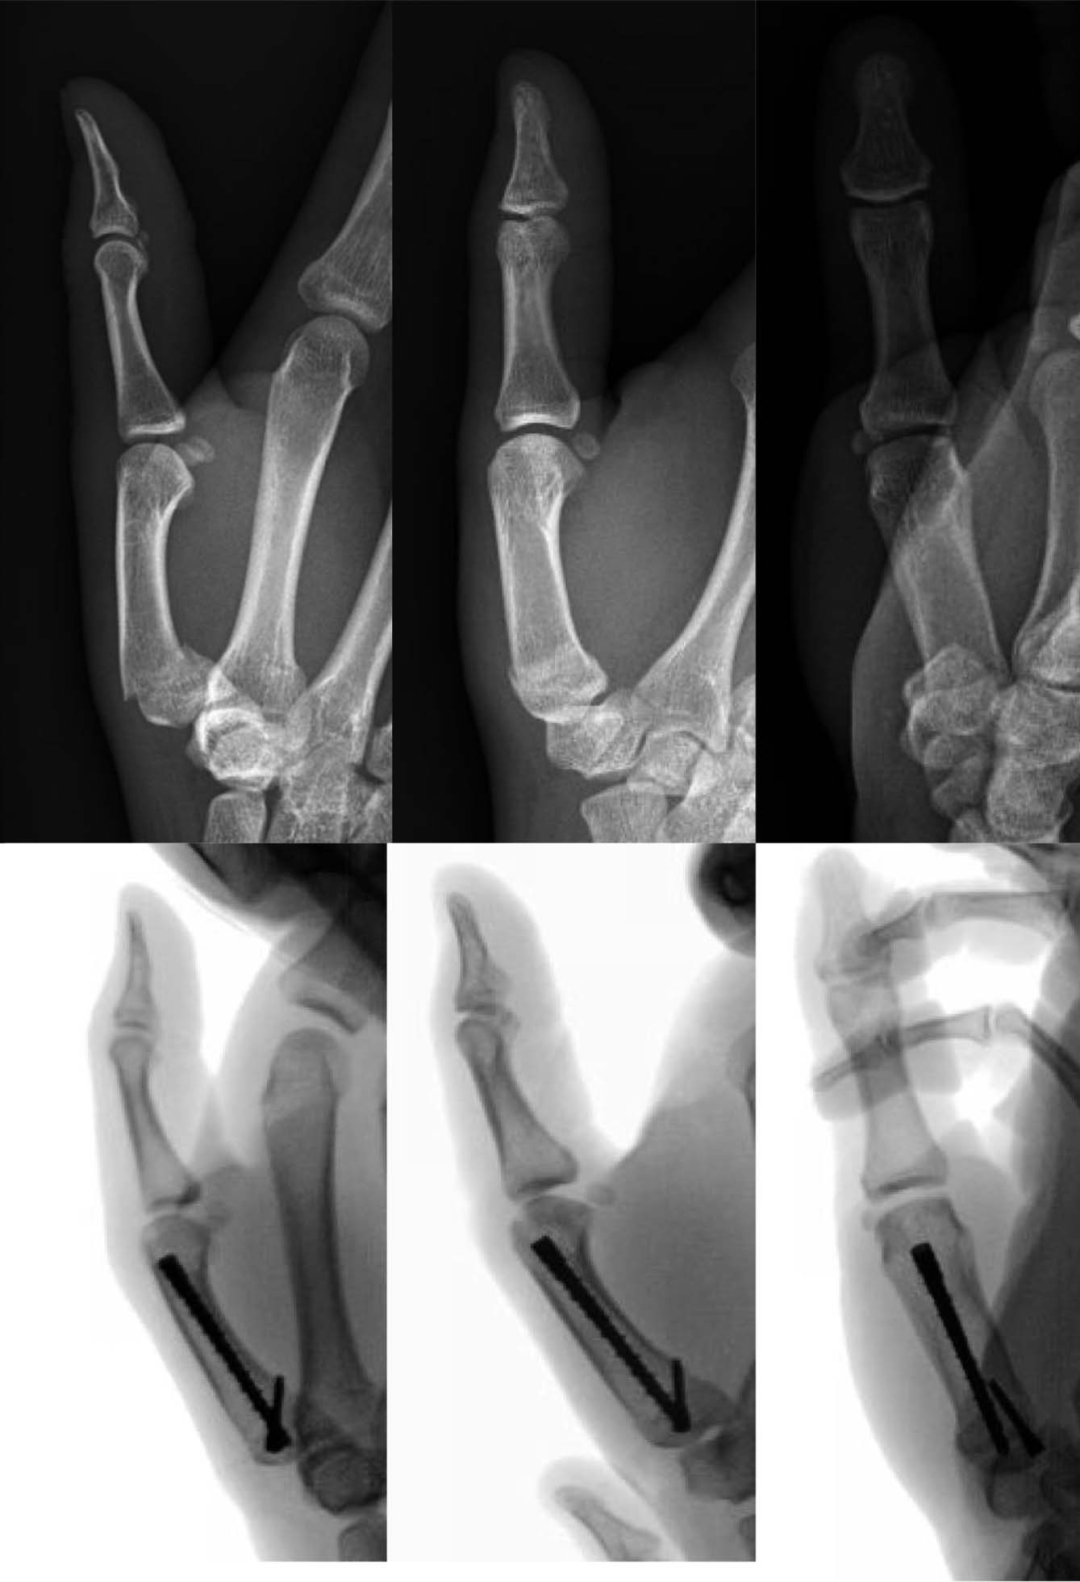

四、掌骨基部骨折

第一掌骨基部骨折对非手术治疗的耐受性更高,因为腕掌骨关节代偿。手术选择包括经皮闭合复位与切开复位和内固定技术,包括骨折间螺钉、钢板和螺钉结构或髓内固定。